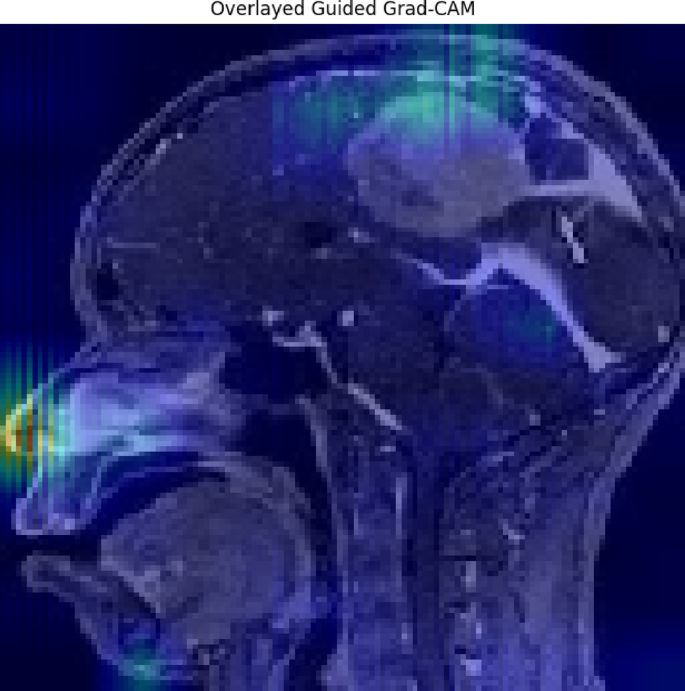

Guided Grad-CAM

The combination of Grad-CAM and guided backpropagation forms Grad-CAM. The areas of an image that prove useful for prediction become Grad-CAM’s main focus while guided backpropagation enhances these results through layer restriction on positive gradients. The approach leads to detailed visualization of image pixels which have maximum impact on the model.

The relevance score Rj for each pixel j is computed as shown in Eq. (40):

This approach provides a more fine-grained explanation of the model’s focus areas, making it easier to validate whether the model is relying on clinically relevant features in the MRI scans35,36.

The technique outlined in this work, called Guided Grad-CAM, merges the benefits of guided backpropagation and Grad-CAM to give a full image of the locations leading to the model’s prediction. The overlay in Fig. 21 shows the specific locations in the brain MRI image that the model is concentrating on, particularly the area surrounding the tumor. The areas receiving the greatest focal point from the model are represented by patches of green and blue, and the overlay demonstrates how these areas impact the decision class. This method provides a more complete and accurate explanation for why a model is seeing what it sees to ensure that the model’s focal point is clinically aligned. In this study, LIME is used to identify the decision boundaries of the ensemble model as further evidence of the ways these different features drive one classification decision to the next. In Fig. 22, using LIME, this study provides an interpretable explanation for the model’s prediction of class 2. The red and green markings highlight which parts of the MRI image contributed most to the classification decision. Certain red sections are damaging to the prediction, while the green sections pose a positive increase to the prediction. As a byproduct of perturbing the original image and then testing how those perturbed images change the model’s decision, LIME enables, even approximates identification of the decision boundary by providing explanations of why this model predicted that class. This kind of openness gives physicians the ability to evaluate whether the model’s prediction is consistent or reasonable with medical expertise.

Guided Grad-CAM XAI heatmap.